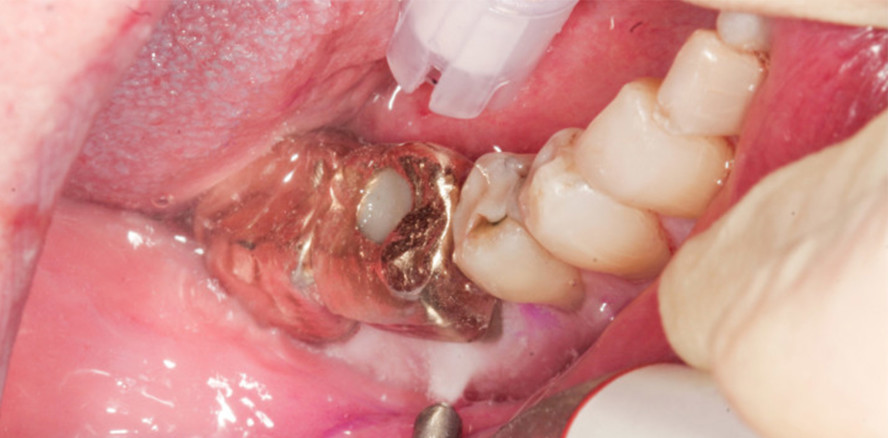

Nur so können erneute parodontale Entzündungen verhindert und einer möglichen Progression der Erkrankung zuvorgekommen werden.10 Dabei können sowohl Handinstrumente oder maschinelle Schall- bzw. Ultraschallscaler zur Entfernung von mineralisierten und nicht mineralisierten Biofilmen als Methode des konventionellen mechanischen Debridements zum Einsatz kommen (Abb. 4a und b).11,12 Für nicht mineralisierte Biofilme nimmt das sogenannte Air-Polishing einen immer größer werdenden Stellenwert ein.13 Jedoch sind, um das umliegende Hart- und Weichgewebe nicht zu traumatisieren, nur niedrigabrasive Pulver zur Behandlung von Biofilmen auf Zahn- und Wurzeloberflächen geeignet (Abb. 4c und d).13,14 Dies können z. B. Glycin- oder Erythritpulver sein, die beide nachweislich eine schnelle und zuverlässige Entfernung supra-/subgingivaler Biofilme bei einem hohen Maß an Komfort bieten.14,15 Entsprechend aktueller Studien ermöglichen weiter- entwickelte Pulver mit verringerter mittlerer Korngröße (z. B. bei Glycin ca. 25 μm bzw. Erythritol ca. 14 µm) eine maximale Schonung der Weich- und Hartgewebe bei gleichzeitigem maximalem Reinigungseffekt.16–18 Jedoch wird die Methode teils kontrovers in der Wissenschaft diskutiert, gerade auch, weil beispielsweise nur wenig Erkenntnisse zu den klinischen Vor- und Nachteilen des Air-Polishing-Verfahrenes in morphologisch komplexen Bereichen, wie der Furkation gegenüber dem konventionellen Instrumentieren mit Handküretten/maschinellen Scalern und klassischer Politur im Rahmen der UPT, vorliegen.19 Verschiedene aktuelle klinische Studien griffen das Thema auf. So zeigten Petersilka et al. (2021) über einen mittleren Beobachtungszeitraum von fünf Jahren, dass Molaren mit Furkationsbeteiligung einen Trend zur Verschlechterung des Furkationsstatus aufwiesen, wenn sie in der UPT ausschließlich mit einem supragingivalen Düsenkopf im Vergleich zur konventionellen Reinigung mit Küretten und maschinellen Scalern gereinigt wurden.12 Ein möglicher Grund für diesen negativen Trend könnte darin bestehen, dass in der Studie ausschließlich supragingivale Düsen verwendet wurden und kein Aufsatz speziell für tiefere Taschen. Eine andere Studie von Ulvik et al. (2021) untersuchte die Veränderung klinischer Parameter bei Verwendung von Erythritolpulver gegenüber Kürette und Ultraschallscaler bei der Behandlung von Unterkiefermolaren mit Furkationsgrad II in der UPT.20 Die Autoren fanden trotz der Verwendung einer speziellen subgingivalen Düse während des Air-Polishing nach sechs Monaten Beobachtungszeit einen signifikanten Unterschied im klinischen Attachmentlevel zugunsten der Kürette und Ultraschallscalergruppe. Auf Basis dieser eher ernüchternden klinischen Behandlungsergebnisse stellte sich eine Kieler Arbeitsgruppe21 die Frage nach möglichen Ursachen dafür und entwickelte ein In-vitro-Modell, um unter reproduzierbaren Versuchsbedingungen die Effektivität der subgingivalen Biofilmentfernung mit zwei verschiedenen maschinellen Scalern (Schall- und Ultraschall) im Vergleich zu zwei verschiedenen Air-Polishing- Geräten mit und ohne subgingivale Düsenansätze an Molaren mit durchgehenden Furkationen zu untersuchen.22 Auch die Kieler Arbeitsgruppe konnte in der experimentellen Untersuchung zeigen, dass mittels maschineller Scaler eine bis zu 1,7-fach höhere Reinigungsrate des Furkationsbereichs gegenüber der Air-Polishing-Methode möglich ist, wobei der Schallscaler mit einer filigranen Parospitze (1AP, W&H) rund 46 Prozent aller Flächen des Furkationsbereichs suffizient zu reinigen vermag.21 Nur ein Air-Polishing-Gerät mit starrer subgingivaler Düse unter Verwendung von Glycinpulver (LM-ProPowerTM, LM-Instruments Oy; Abb. 3a) zeigte eine vergleichbar hohe Reinigungsleistung bei gleichzeitig 1,3-fach verkürzter Behandlungszeit. Jedoch musste auch festgestellt werden, dass die Air-Polishing-Methode im Vergleich zum konventionellen Instrumentieren mit maschinellen Scalern bei Molaren mit Furkationsbeteiligung weitgehend schlechter abschnitt und somit den zitierten klinischen Behandlungsergebnissen entsprach.11,20 Eine mögliche Ursache dafür wurde im Design einer der getesteten Düsen zur subgingivalen Reinigung gefunden. Diese zerstäubt den Pulver-Wasser-Strahl großflächiger auf der Wurzeloberfläche bei gleichzeitigem vertikalem Wasserstrahl, um den sogenannten „Fließdruck“ zu reduzieren (Abb. 3b), wodurch eine besonders schonende Entfernung für Hart- und Weichgewebe des subgingivalen Biofilms im Zahnfleischsulkus ermöglicht wird. Dies scheint sehr vorteilhaft im entzündeten Weichgewebe (z. B. Vorbeugung von Emphysemen), jedoch entsteht dadurch auch ein reduzierter Druck des Reinigungsstrahls, der nun womöglich nicht mehr ausreichend „Kraft“ besitzt, um alle Bereiche der Furkation zu erreichen bzw. den etablierten Biofilm vollständig zu entfernen.18,21 Möglicherweise schneiden deshalb speziell für die subgin- givale Instrumentierung entwickelte Düsen im Bereich des Furkationsdachs schlechter ab, als es deren Design mit Zugang in tiefere Bereiche des Zahnfleischsulkus erwarten lassen. Jedoch sei angemerkt, dass diese Düsen primär für tiefe schmale Knochentaschen und nicht für den Furkationsbereich entwickelt worden sind.23 Die Anwendung dieser subgingivalen Düsen im engen Furkationsbereich gestaltete sich umständlich, teils verbogen die flexiblen Düsen bei der Arbeit in der Furkation schnell, was eine genaue „Ansteuerung“ der Wurzeloberfläche nahezu unmöglich machte und als weiterer Erklärungsansatz für die geringe Reinigungseffektivität interpretiert wurde (Abb. 3).

Allerdings kam bei der experimentellen Untersuchung eine eng anliegende Gingivamaske erschwerend hinzu, wodurch mitunter die subgingivale Instrumentierung mit den subgingivalen Düsen deutlich behindert wurde. Jedoch betraf dies auch die Handhabung der maschinellen Scaler, deren Schwingungsfrequenz und -amplitude ebenfalls gehemmt wird.24 Es sollte aber auch bedacht werden, dass eine ebensolche straffe Gingiva häufig im Rahmen der UPT vorhanden ist. Gemäß der aktuellen S3-Leitlinie9 können Parodontitispatienten mit reduziertem, aber gesundem Parodont oder mit gingivaler Entzündung in der UPT unterschieden werden, was in beiden Fällen jedoch auch in der Praxis eine ausreichende Penetration der subgingivalen Düse von Air-Polishing-Geräten in die Furkation voraussetzt (Abb. 4).